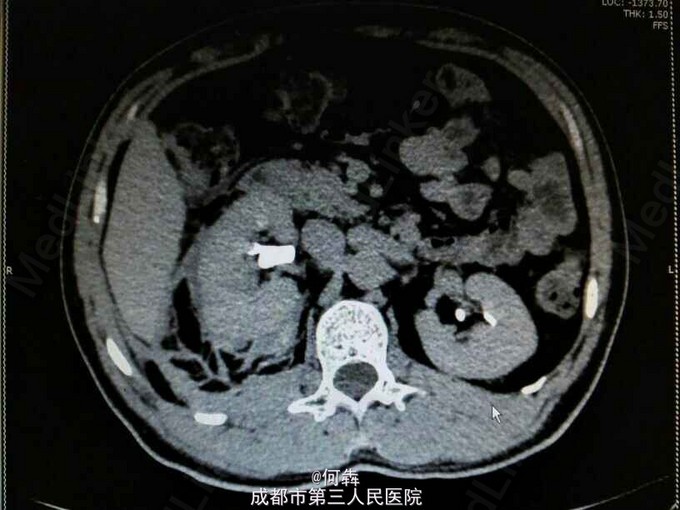

48岁男性,因“突发右腰痛1小时”入院,无血尿、外伤。既往无高血压、糖尿病。

右肾区扣痛阳性,余阴性。

右肾占位伴出血。入院后6天在全麻下行右肾部分切除术。术中冰冻及术后病检见图片